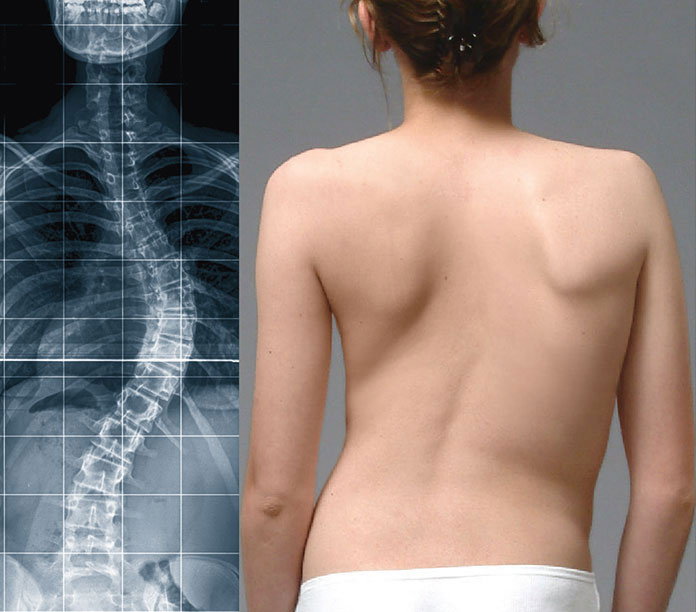

Искривление позвоночника: причины и последствия на снимках

Раздел: Визуальный дайджест